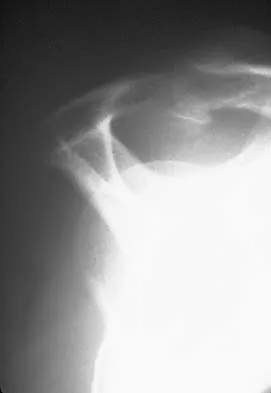

A 22-year-old motorcyclist is brought in after a high-speed collision. He has an entirely flail, pulseless upper extremity. Radiographs shown in

demonstrate significant lateral displacement of the scapula. What is the most critical immediate step in management?

Explanation